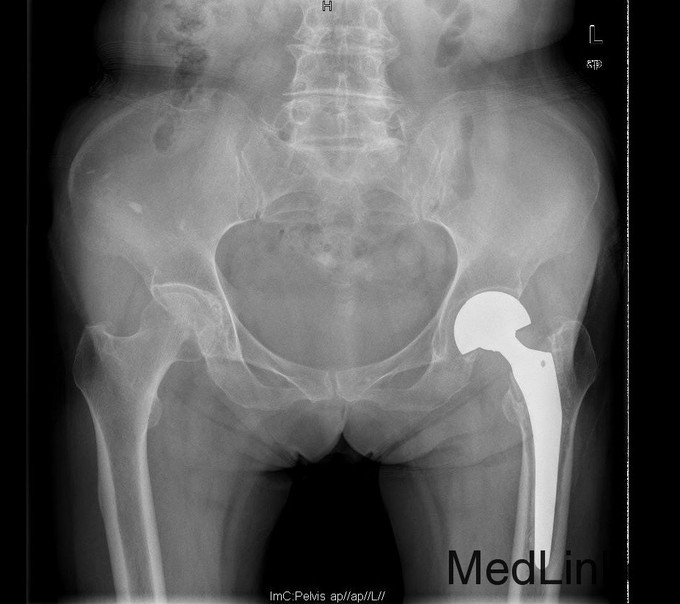

诊断:左双动股骨头置换术后假体松动、下沉、股骨骨缺损(PaproskyII型) 治疗:患者在全麻下左双动股骨头假体取出+同种异体骨植骨+左全髋关节翻修术,术后予以抗炎(二联)+抗凝+镇痛+护胃+补液等治疗,并予以抗骨质疏松药物

出院时左髋可屈曲90°,伸直0°,外展30° 讨论: 1、髋臼侧是否置换关键看什么? 2、Paprosky分型? 3、高龄患者行骨科大手术围手术期应着重注意哪些方面?( 体力、肺部感染、液体量与心功能、营养与饮食、锻炼与下肢深静脉血栓~~~~~) 4、假体柄的选择有何要求? 5、术后1天与术后3月的片子有何差别,试分析原因